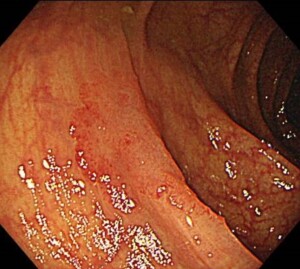

陥凹型は割合が少なくたまにしか遭遇しません。これは比較的見つけやすい陥凹型ポリープです。周辺に比べて中央がわずかにくぼんでいます。このサイズで早期大腸がんでした。

平坦型は見つけづらく見逃しやすいものになります。わずかな色の違い、血管模様の違いなどから見つけていきます。